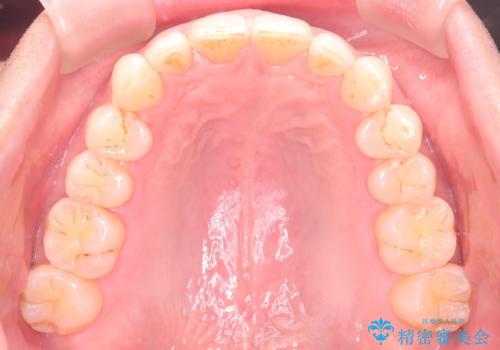

【インザライン】前歯の凸凹を治したい

- 前歯の凸凹を主訴に来院されました。

下顎位が右方に変異しており、外科矯正も提案しましたが患者様は希望されず、インビザラインにて治療を完了しております。

叢生のスペースを確保するために、臼歯部の遠心移動を行っています。

今回の治療計画は上顎の正中を顔と揃えることを優先しています。